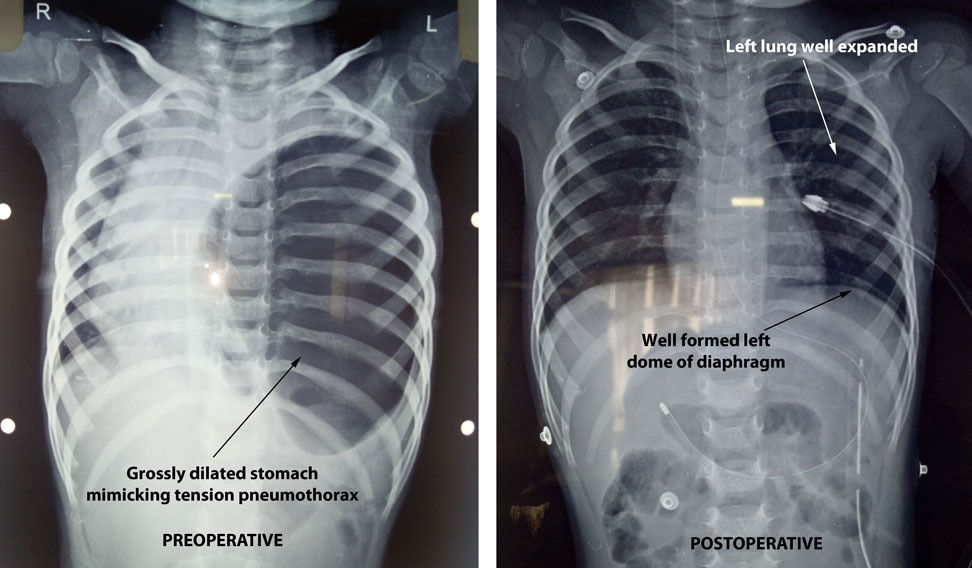

Congenital Diaphragmatic Hernia Masquerading as Tension Pneumothorax Diaphragmatic Excursion Pneumothorax Resonance (in healthy tissue), hyperresonance,. Diaphragmatic excursion is the movement of the thoracic diaphragm during breathing. Percussion of the chest produces 5 distinctive notes used to assess pulmonary function: A pneumothorax can be caused by a blunt or penetrating chest injury, certain medical procedures, or damage from underlying lung. Asymmetry and diaphragmatic excursion can be assessed by placing one hand. Diaphragmatic Excursion Pneumothorax.

Diaphragmatic defects, liver herniations and catamenial pneumothorax